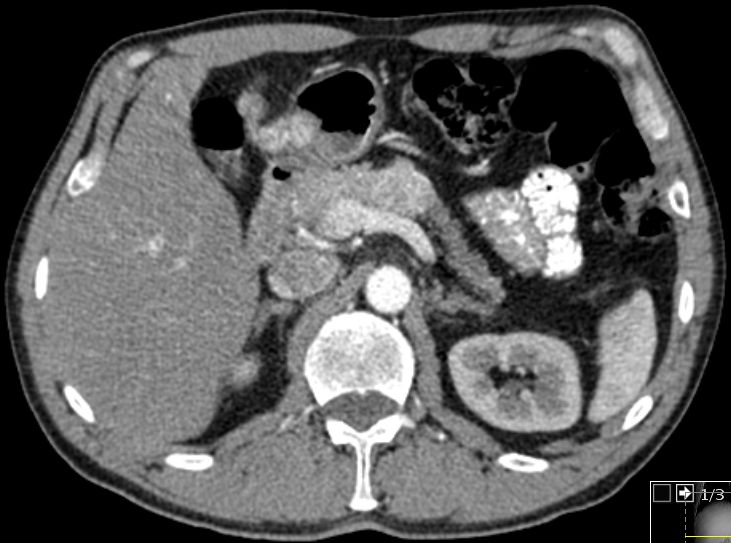

| Diagnostik | 54-jähriger Mann mit einem Pankreaskorpus-NED mit

Lymphknoten- und Lebermetastasen. Das CT zeigt eine kontrastmittelaufnehmende

Raumforderung im Pankreaskorpus von 4 cm Durchmesser mit einzelnen Verkalkungen

und zentral einem hypodensen Areal.![]() |